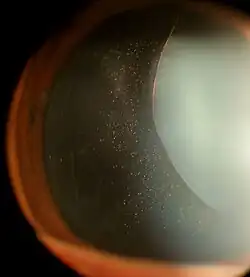

Ectopia lentis in a patient with Marfan syndrome. Zonular fibers are visible. | |

Ectopia lentis is a displacement or malposition of the eye's lens from its normal location. A partial dislocation of a lens is termed lens subluxation or subluxated lens; a complete dislocation of a lens is termed lens luxation or luxated lens.